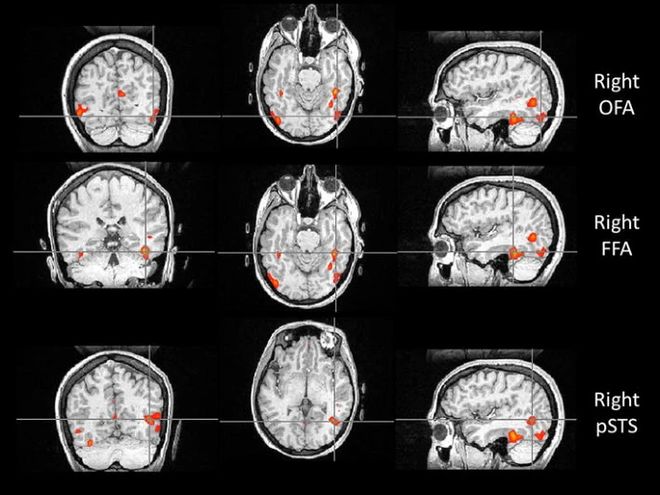

比如,位于枕叶的枕叶面孔区(Occipital Face Area, OFA),就像识脸网络的“先锋部队”。它专门处理眼睛、鼻子和嘴巴等五官“零部件”。当一张脸出现在我们眼前时,OFA 只需 约 100 毫秒 就能被激活,迅速对局部特征进行拆解,并将信息传递给 FFA 和上颞沟(Superior Temporal Sulcus, STS)。所以如果 OFA 出现问题,识别人脸就会变的很困难。

如果说 OFA 的作用是拆解五官,那么 STS 则更像是一个“动态解码器”。它对静态的面孔特征兴趣不大,却对动态特征极为敏感,尤其擅长捕捉一颦一笑、眼神转动、嘴唇开合等细微变化。

正因为有 STS 的参与,我们不仅能认出“这是谁”,还能理解“他在表达什么情绪”“注意力投向哪里”,甚至在一定程度上推测对方的意图。STS 的参与也解释了 why比起静态照片,在现实生活或视频中,我们更容易认出熟人。

与认脸有关的三个核心脑区,自上而下依次为:OFA(枕叶面孔区)、FFA(梭状回面孔区),以及 STS(上颞沟)。图片来源:doi: 10.1007/s00221-011-2579-1